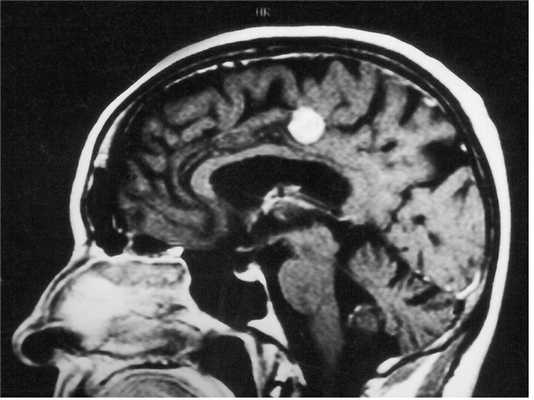

МРТ головного мозга. Менингиома свободного края намета мозжечка (область шишковидной железы). Сагиттальные Т1-зависимые МРТ до и после контрастирования.